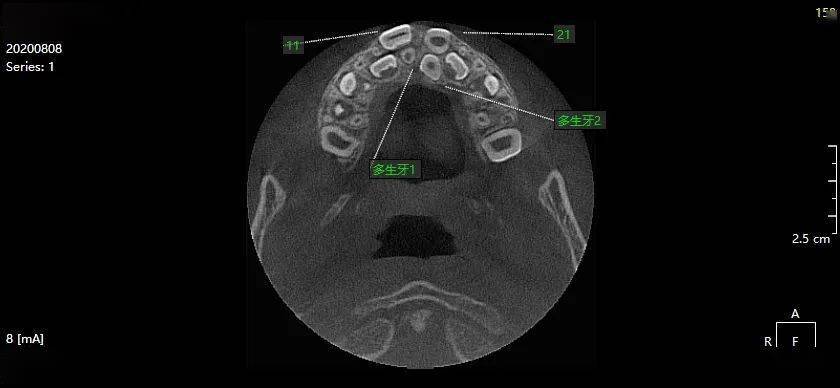

黄xx 20200808 多生牙cbct 137xxxx7962

图片尺寸840x388